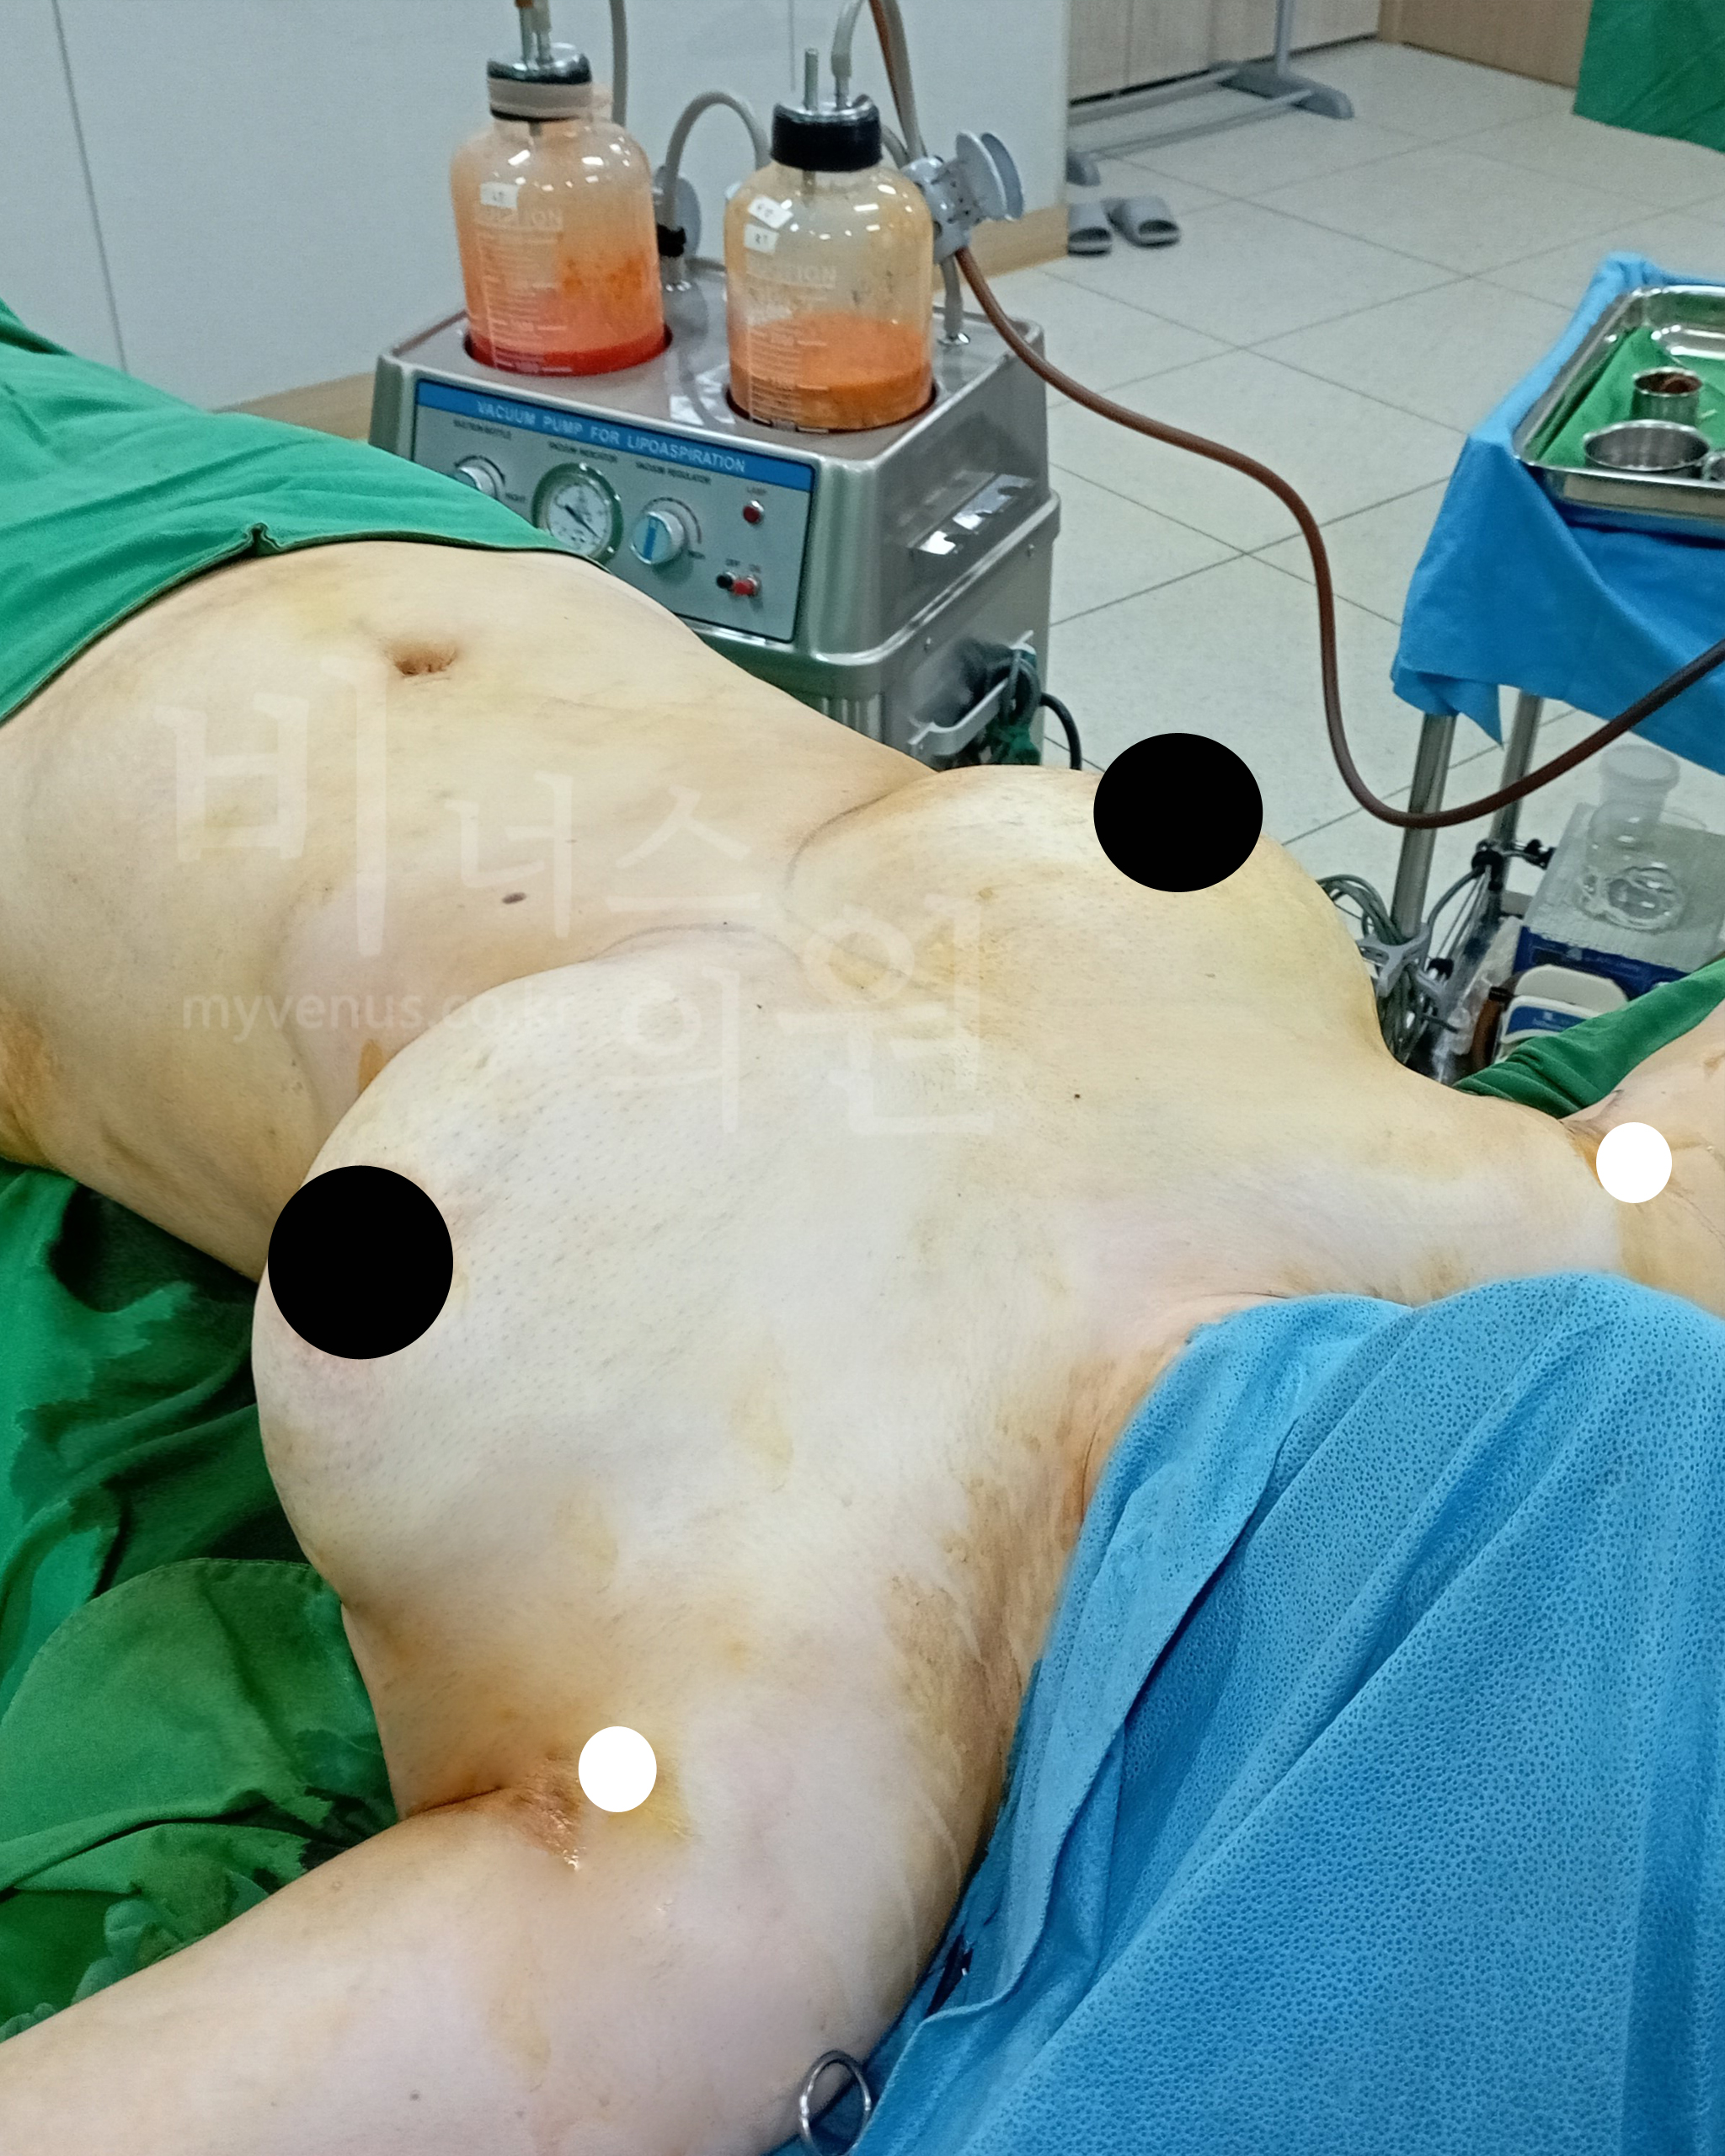

투메슨트 용액을 주입하고 있는 모습

양쪽 가슴이 빵빵하게 부풀려진 모습

안전한 투메슨트 가슴축소 지방흡입은 용액을 지방조직에 주입하고 지방세포가 부풀어지면 지방 조직을 흡입하는 방법이에요. 지방조직이 혈관을 수축시키고 동시에 부풀려진 지방을 흡입하기 때문에 출혈이 적어요. 수술 후에도 국소마취제가 지방층에 남아있어 추가적인 진통제 주사 없이도 수술 후 통증이 일반적으로 없어요.

최소의 절개를 내어 가슴지방흡입하는 모습

가슴의 지방이 흡입되고 있는 모습